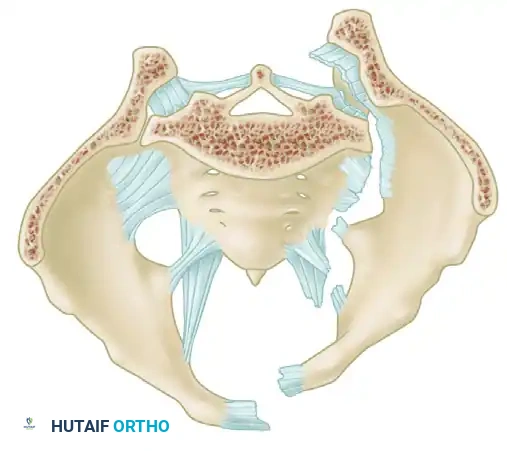

A profound understanding of pelvic osteoligamentous anatomy is the foundation of both classification and treatment. The pelvis is a ring structure composed anteriorly of the pubic and ischial rami connected at the symphysis pubis. A fibrocartilaginous disc separates the two pubic bodies, providing a degree of physiologic elasticity.

Posteriorly, the sacrum and the two innominate bones are joined at the sacroiliac (SI) joints. The SI joint itself possesses no inherent bony stability; its integrity relies entirely on a massive, complex ligamentous network.

The Posterior Tension Band

The posterior ligamentous complex is the primary weight-bearing and stabilizing structure of the pelvis. Tile famously compared the relationship of the posterior pelvic ligamentous and bony structures to a suspension bridge, with the sacrum suspended securely between the two posterior superior iliac spines.

The critical ligaments include:

* Interosseous Sacroiliac Ligaments: The strongest ligaments in the body, forming the primary restraint to vertical shear forces.

* Anterior and Posterior Sacroiliac Ligaments: Provide rotational stability to the SI joint.

* Sacrotuberous Ligaments: Resist rotation in the sagittal plane (flexion of the sacrum).

* Sacrospinous Ligaments: The primary restraints to external rotation of the hemipelvis.

* Iliolumbar Ligaments: Connect the L5 transverse process to the iliac crest, augmenting vertical and rotational stability.

Biomechanical Restraints

Pelvic stability is determined by these ligamentous structures acting across various planes. The primary restraints to external rotation (the "open book" deformity) are the ligaments of the symphysis, the sacrospinous ligament, and the anterior sacroiliac ligament. Vertical displacement of the hemipelvis is controlled by all the aforementioned structures. However, if the anterior structures are disrupted, vertical stability may still be maintained by intact interosseous sacroiliac, posterior sacroiliac, and iliolumbar ligaments.